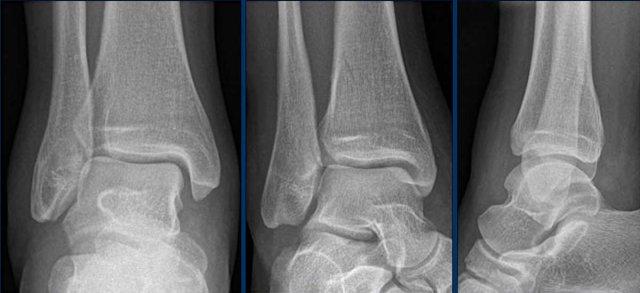

Ca 3 – Chấn thương cổ chân

Hình ảnh cho thấy những dấu hiệu gì?

Phân độ tổn thương trong trường hợp này là gì?

Nhấp vào hình ảnh để xem phóng to.